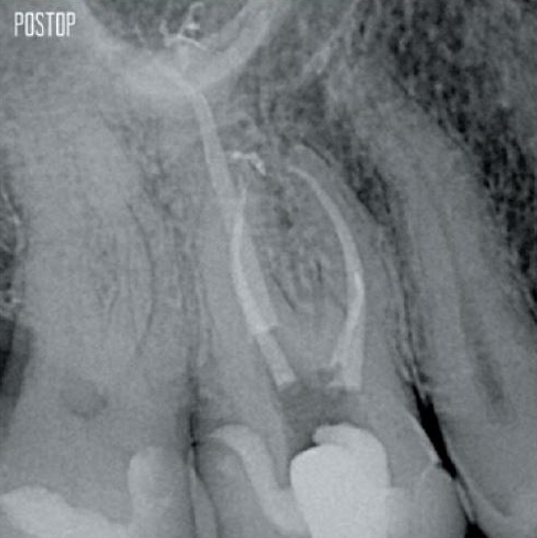

Fotos cortesia do Dr. Ahmed Salman

A união da geometria da lima, as conicidades regressivas e o fio fino e altamente flexível permitem um tratamento eficiente do canal radicular, removendo a dentina apenas onde for clinicamente necessário.1

O acesso agora é possível a partir de diferentes ângulos, enquanto até agora a estrutura precisava ser sacrificada (cavidade endodôntica tradicional).1

Não há necessidade de acesso linear.1